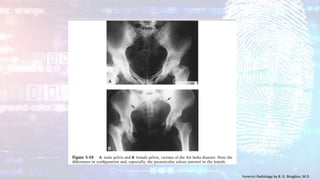

Sex Determination- Pelvis

The bony pelvis often survives the attack of factors which diminish or

destroy the usefulness of other body parts. This is fortunate since the

pelvis offers the most definitive traits of sexual

differentiation

• The subpubic arch (subpubic concavity) is narrow and triangular with an

inverted V-shape in the male and broad and with an inverted U-shape in

the female.

• The pubic bone tends to be long and narrow in the male and broad and

rectangular in the female.

• The sciatic notch is deep and narrow in the male, and is wide and shallow

in the female.

• The preauricular sulcus (paraglenoid sulcus) when present is one of the

most dependable indicators of femaleness. This variable groove in the

ilium at the inferior end of the sacroiliac joint is missing or manifest very

rarely as a thin groove in the male, and a deep groove is found only in

females.

• The ilial alae are high and vertical in the male, and broad and laterally

divergent in the female.

• The sacrum in the male is narrow, has a relatively flattened curve. The

female sacrum is broad and short.

• The pelvic inlet is triangular or heart-shaped in the male, ovoid in the

female.